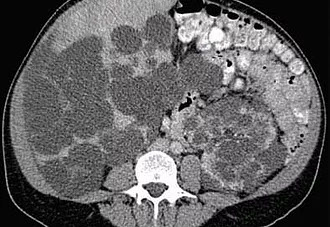

Enfermedad Hepática Poliquistica

La enfermedad poliquística hepática aislada (PCLD) es un trastorno genético que se caracteriza por la aparición de numerosos quistes por todo el hígado y que en la mayoría de los casos se describe como una enfermedad poliquística hepática autosómica dominante (ADPCLD).

Afecta con mayor frecuencia a mujeres que a hombres. Los quistes suelen aparecer después de los 40 años de edad y no son detectables antes. Su número y tamaño se incrementa con la edad. Los síntomas dependen de la masa (efecto de compresión) y pueden incluir distensión abdominal, reflujo gastro-esofágico, saciedad precoz, disnea, disminución de la movilidad y dolor en la espalda por la hepatomegalia. Algunos pacientes están asintomáticos.